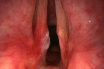

Either of two folds of tissue, each containing an elastic tissue known as the vocal ligament, that protrudes from the sides of the larynx forming a narrow slit in the larynx, called the glottis. As air is exhaled through the larynx, the vocal cords vibrate, producing sound. Movements of the tongue, lips, jaws, and accessory mouth structures mold the column of air passing through the glottis, producing sounds of different intensity and pitch.

Two folds of mucous membrane over- lying two vocal ligaments in the larynx (voice box) that vibrate to produce the sounds of speech. Most of the time the vocal cords lie apart, forming a triangle-shaped opening through which air passes for breathing. The cords also close automatically during swallowing to prevent food from going down the trachea instead of the esophagus.

The two folds of tissue that protrude from the sides of the larynx to form a narrow slit (glottis) across the air passage. Their controlled interference with the expiratory air flow produces audible vibrations that make up speech, song, and all other vocal noises. Alterations in the vocal cords themselves or in their nerve supply by disease interferes with phonation.

To create sound, the vocal cords, which usually maintain a V-shaped gap, come together and oscillate when air is pushed out from the lungs through them. Changes in the tension of the cords result in varying pitches, and these sounds are further shaped by the tongue, mouth, and lips to form spoken language.